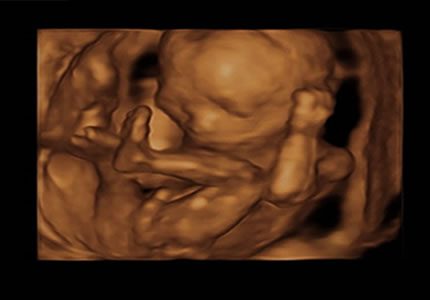

4D Bonding Experiences (24 – 34 Weeks)

Enjoy a magical glimpse of your baby’s face in real time. Ideal during 26–30 weeks when fluid and positioning are optimal.

- Utilising our advanced imaging technology, we offer you a magical window into your baby’s world. You can watch your baby’s real-time expressions, such as yawning or smiling. This session is best booked between 26–30 weeks when the baby has developed enough features for clear, detailed viewing.

- £119